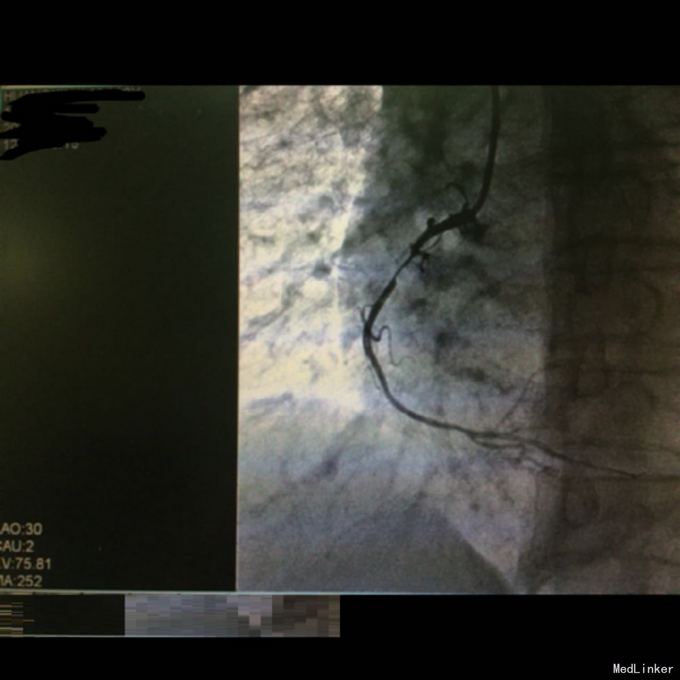

查体:生命体征平稳。双肺呼吸音粗,双下肺可闻及湿性啰音。 辅查:急诊CAG+PCI见右冠近段狭窄约90%,遂置入药物支架一枚,造影显示远端血流达TIMI3级。复查心电图示下璧心梗。